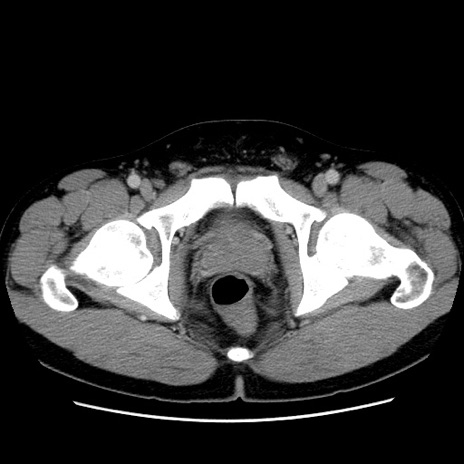

症例4(横断像)

【症例】30歳代男性

【主訴】腹痛、嘔吐

【現病歴】昨晩から突然の腹痛あり、その後嘔吐、軟便も出現。腹痛が改善しないため救急搬送となる。2日前にしめ鯖の食事歴あり。

【身体所見】意識清明、苦悶様、BP 135/90mmHg、BT 35.7℃、腹部:平坦、やや硬、心窩部〜臍部に自発痛、圧痛あり、筋性防御+、反跳痛-

【データ】WBC 8100、CRP 0.57